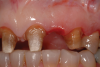

A patient presented with two defective 3-unit fixed partial dentures spanning teeth Nos. 6 through 8 and teeth Nos. 9 through 11 (Figure 7). The defective fixed partial dentures were removed (Figure 8), an impression was made, and traditional provisional fixed partial dentures without ovate pontics were placed. After the impression was sent to the laboratory, the lab technician prepared ovate pontic sites on the stone cast (Figure 9) and fabricated the new definitive bridges. On the day of insertion, the provisional fixed partial dentures were removed (Figure 10), ovate pontic sites were prepared using a teardrop-shaped diamond bur (Figure 11), and the sites were sounded to confirm that there was at least 2 mm from the base of the pontic site to the alveolar bone (Figure 12). The fixed partial dentures were cemented, and the postoperative healing was uneventful (Figure 13).

(10.) Close-up view of the existing edentulous tooth No. 10 site prior to the creation of the ovate pontic site.

Figure 10

(11.) Close-up view of the preparation of the ovate pontic sites.

Figure 11